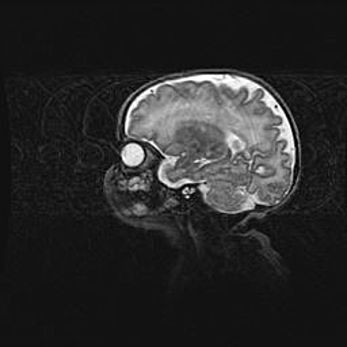

Неполная лизэнцефалия (пахигирия). Открытая гидроцефалия.

Возраст: 17 дней

Вес: 3110 г

Пол: мужской

Окружность головы: 33,5 см

Срок гестации: 35-36 недель

Лизэнцефалия—недоразвитие корковой пластинки и мозговых извилин в результате нарушения миграции нейронов коры. Поверхность мозговых полушарий гладкая. Микроскопически выявляется отсутствие нормальных слоев коры и скопление групп нейронов в подкорковом белом веществе.

Пахигирия—уменьшение числа вторичных извилин. В пораженном полушарии нервные клетки образуют толстый недифференцированный слой с неправильно расположенными нервными волокнами и группами гетеротопных клеток. Нервные клетки незрелые. Белое вещество истончено. При этом нередко аномально развит корково-спинномозговой путь.